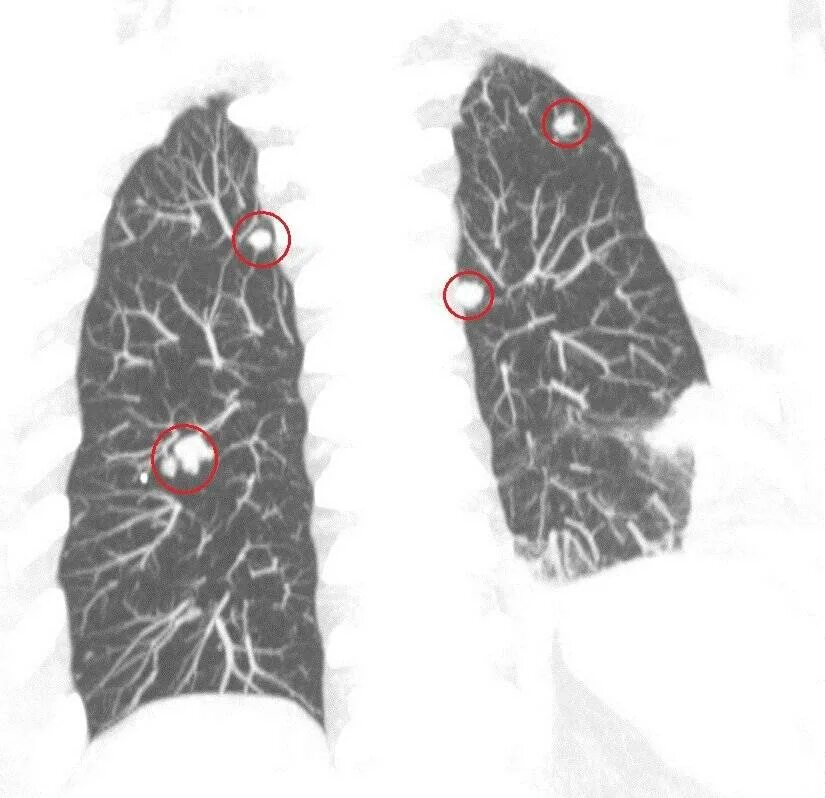

Метастазы в легких терапия